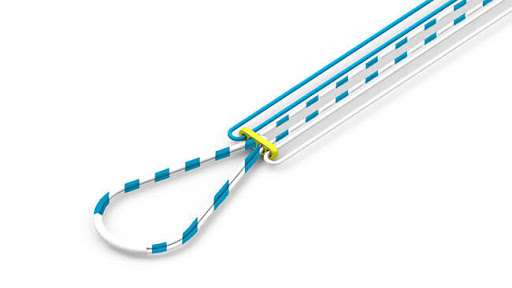

Placa Endobutton Ajustável

A Placa de Reconstrução Ligamentar é um dispositivo implantável, não ativo, invasivo cirurgicamente e de uso único. Desenvolvida para garantir a reconstrução do ligamento cruzado anterior e posterior.

- Fio de Sutura UHMW PE USP – Ø 0,5 mm

Seu projeto inovador permite o ajuste da sutura pelo cirurgião, o que garante maior precisão no balanceamento ligamentar sem que haja a necessidade de realizar os cálculos para determinar o tamanho da laçada e profundidade.